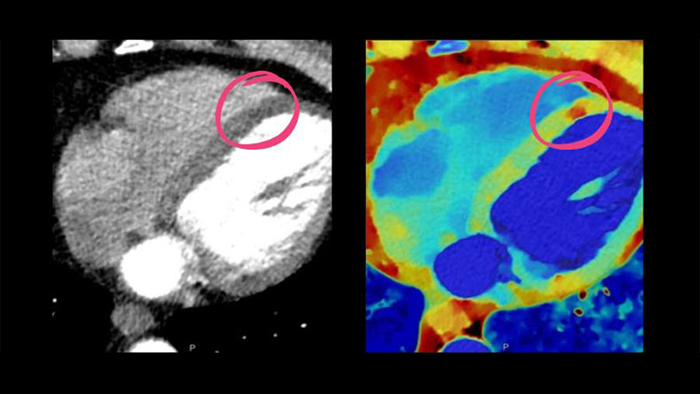

See beyond routine cardiac imaging with the additional clinical information of Spectral CT for advanced cardiac applications. Learn how the Spectral CT 7500's "Always On" Spectral CT workflow helps you meet the needs of all your patients with zero compromises.